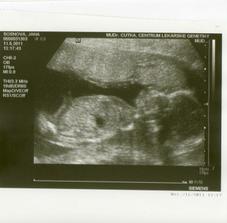

11.5.2011 velký UZ v ČB, potvrzena holčička, taťkovi se taky moc líbilo